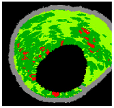

Figure 7 depicts the effectiveness of the KMPSO-mED model by segmenting the overlapping tissues in VH-IVUS images.

Figure 7.

Segmentation by KMPSO-mED: (a) overlapped tissue, and (b) segmented area.

To investigate the consistency of the proposed KMPSO-mED model using different plaque types, several real VH-IVUS images were tested and the results compared. Table 3 shows the segmentation results achieved by the KMPSO-mED model for 9 VH-IVUS images.

Table 3.

Results of VH-IVUS segmentation by KMPSO-mED, (SW: Silhouette Weight).

When the clustering processes are completed, the correctness of each clustering technique is validated by silhouette index [76]. The silhouette value of each pixel shows its similarity with other pixels belonging to this cluster in comparison with pixels belonging to other clusters. The range of silhouette value varies from −1 to +1. Higher average silhouette values indicate higher clustering accuracy [77]. Based on Table 2, all obtained SW show the high accuracy rate of the clustering process. Images 1 to 6 involve four plaque components. Therefore, KMPSO-mED segmented these images into FF, FI, NC, and DC. Images 7 and 8 have three components; these images are segmented into FF, FI, and NC. Image 9 is segmented into two different segments, namely FF and FI. The results show that the proposed model can successfully classify the pixels of overlapping regions. Moreover, the KMPSO-mED model has the potential to segment VH-IVUS images with different numbers of clusters.